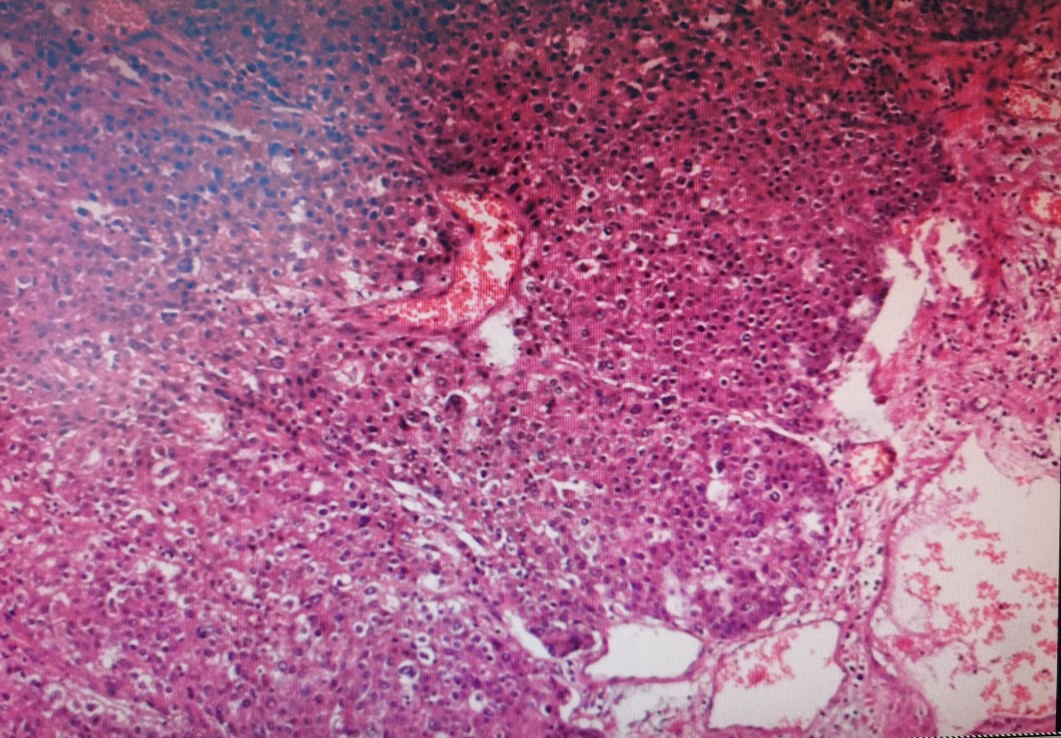

从术后病理看王老得的是一种非常罕见的肿瘤,贲门肝样腺癌。肝样腺癌是一种与原发性肝细胞肝癌具有极为相似的形态学特征的肝外恶性肿瘤,临床上在胃、直肠、胆囊、肺、卵巢、膀胱等均有病例报道,但病例数量较少。其中胃肝样腺癌是最常见的一种肝样腺癌,是胃癌的一种亚型,常伴有血清甲胎蛋白(AFP)升高,容易导致误诊和漏诊,临床上需要病理和免疫组化资料来确诊。此病相比普通胃癌更具侵袭性、对化疗药物不敏感,靶向药物治疗目前处于探索阶段,中医中药应该有一定的作用。因为年龄太大,王老术后没有做放化疗,我建议他老伴到我一个朋友(著名消化道疾病中医专家于振宣)那里看看,让他给开点中药调理一下,一来是改善一下饮食和食管反流的情况,另外一个也是针对这个肿瘤做一些治疗。

王老术后病理,只有一个淋巴结转移

术后病理图片,癌细胞像肝癌细胞